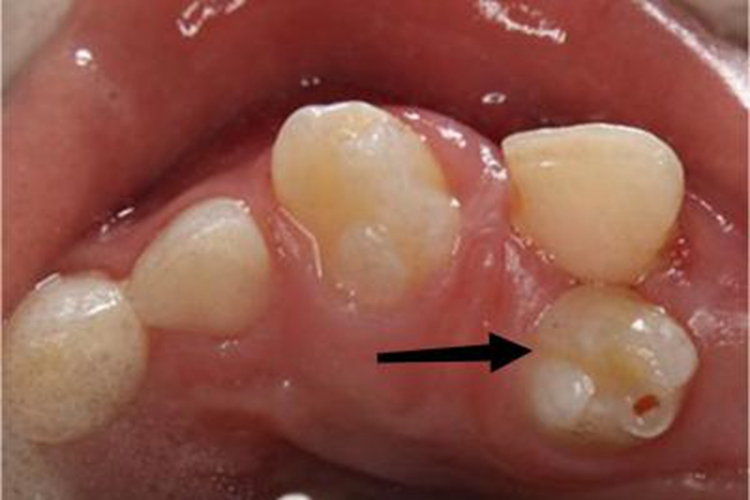

多生牙可表现为牙齿增多,而且形态变异,可呈圆锥形、结节形等,表面光滑,颜色与正常牙齿无异,常可造成牙列拥挤、牙间隙大、牙移位等症状。

对于已萌出的多生牙应及时拔除,拔除需由专业医生操作。如多生牙埋伏在颌骨内,应追踪观察。如未对恒牙产生影响,且无任何病理变化时,可不做处理。